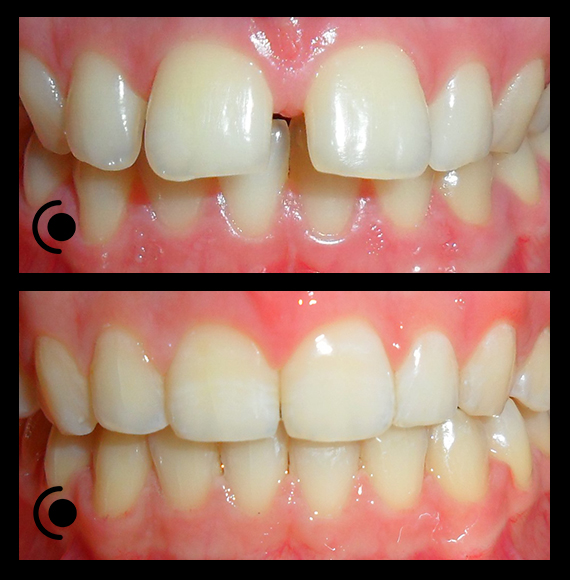

O našoj kvaliteti najbolje govore naši rezultati!